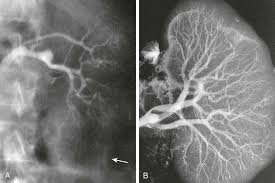

**Perceba na figura do artigo as diferenças:**